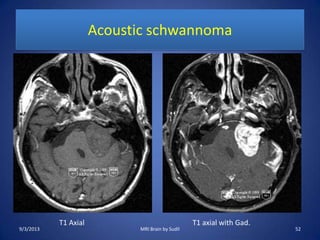

Acoustic schwannoma

T1 Axial T1 axial with Gad.

9/3/2013 52MRI Brain by Sudil